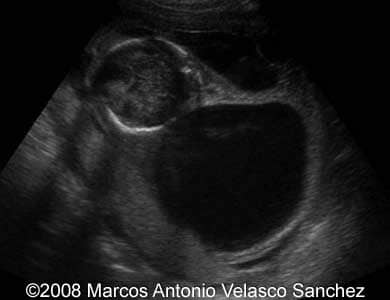

This is a 17-year-old woman scanned at 15 weeks of pregnancy. The ultrasound revealed massive septate cystic hygroma and subcutaneous edema of the fetus.

Images 1-6: 2D scans of the fetal neck with massive septate cystic hygroma.